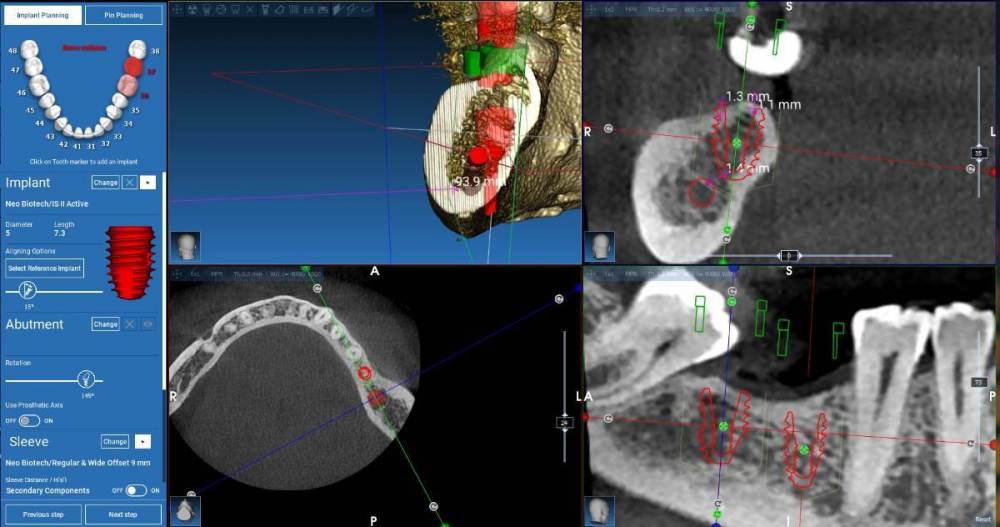

Fin Опубликовано 23 августа, 2023 Автор Поделиться Опубликовано 23 августа, 2023 21.08.2023 в 22:07, stommm сказал: Я нео не работал, но в каталоге видел с 5.0 с шекой 2.3. Попробуйте его нарисовать в планировщике и посмотрите как встанет 21.08.2023 в 21:06, TIGER сказал: @Fin регулярно ставлю 4 и 6 мм ,никаких проблем В моем случае поставили бы два 6мм штраумана? 21.08.2023 в 15:47, koreandr сказал: Так точно) Здравствуйте коллеги. Спасибо за ваши ответы. В планировщике, к сожалению нет импланта 5х7.3 с полировкой но по сути длина такая же. При планировании у пациентки получается перекрестный прикус- так и есть. Подгрузил прикус и немного поправил. Ссылка на комментарий

stommm Опубликовано 21 августа, 2023 Поделиться Опубликовано 21 августа, 2023 6 часов назад, Fin сказал: Спасибо.Вы имеете ввиду диаметр 4.8? Я в Штрауманах плоховато разбираюсь, но для таких клин случаев нужно. Благодарю. Оба Необиотека 5x7.3 с полировкой 1.3? Я нео не работал, но в каталоге видел с 5.0 с шекой 2.3. Попробуйте его нарисовать в планировщике и посмотрите как встанет Ссылка на комментарий

stommm Опубликовано 21 августа, 2023 Поделиться Опубликовано 21 августа, 2023 15 минут назад, TIGER сказал: Для нео 7.3 кости надо 10 мм для заглуба Зачем если шейка 2.3? Ну и судя по скринам влезает по высоте точно. Но тут коронок не видно. Выглядит будто 47 в перекрес выйдёт. Штрауманн тоже можно. Дистально 6 мм. Медиально 6 или 8 (рисовать с учётом коронки и выбирать) Ссылка на комментарий